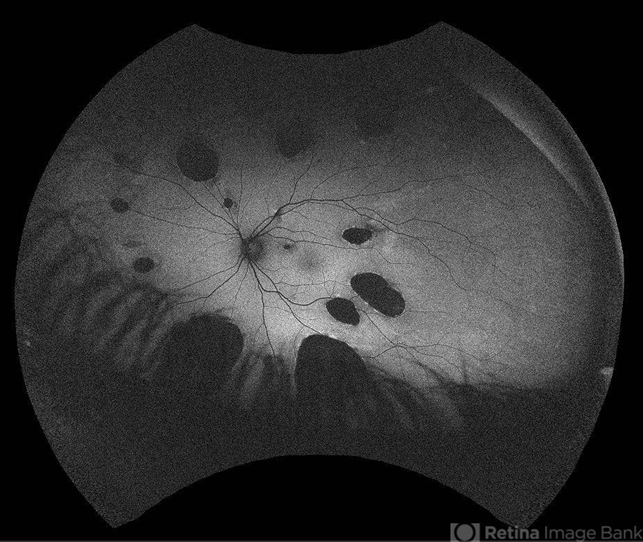

- multifocal choroiditis, multifocal chorioretinitis (MCP), inflammatory choroidopathy

- 23 -year- old man with gradually decreased vision specially in right eye, multiple lesions are in the retinal and choroidal tissue. IMCP causes episodes of inflammation that can occur bilaterally, simultaneously or separately